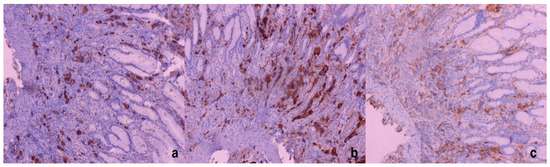

Figure 2. Giant cells—megakaryocytes stained immunohistochemically with Factor VIII (a), CD61 (b), and CD31 (c); ×100.

Figure 3. Giant cells—megakaryocytes immunohistochemically negative for AE1/AE3 (a) with positive internal immunohistochemical control (AE1/AE3 positivity in surface and foveolar epithelium) (×100). In (b), it is shown that giant cells, megakaryocytes, were negative for CD68, in comparison with CD68-positive macrophages (×100). Based on the performed immunohistochemical analysis and giant cell positivity for Factor VIII, CD61, and CD31, the megakaryocytic lineage of the gastric mucosa was confirmed. Because of this giant-cell immunohistochemical positivity, we suspected EMH in the gastric mucosa and, in the meantime, it was revealed that the patient had been treated for osteomyelofibrosis.